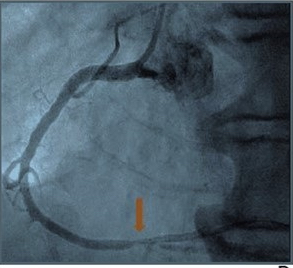

L’étude de la Fractional Flow Reserve (FFR) est un indicateur hémodynamique reconnu dans l’identification d’une sténose coronarienne. Historiquement réalisée à l’occasion d’une coronarographie, elle s’obtient désormais par tomodensitométrie (FFR-CT).

Dans cette étude, 59 patients (46 hommes, 13 femmes ; âge moyen : 66,5 ans) ont subi un coroscanner avec score calcique, suivi dans les 90 jours d'une coronarographie avec mesure de la FFR et d’nstantaneous wave-free ratio (iwFR), de décembre 2014 à octobre 2021. Les lésions coronariennes ont été considérées comme présentant une sténose hémodynamiquement significative en présence de FFR ≤0,80 et/ou iwFR ≤0,89. Un seul cardiologue a évalué les images de coroscanner à l'aide d'un algorithme semi-automatisé basé sur le deep learning pour déterminer la FFR-CT pour les lésions coronariennes détectées par angiographie invasive.

Ensuite, le temps pour l'analyse FFR-CT a été enregistré. L'analyse FFR-CT a été répétée par le même cardiologue dans 26 examens sélectionnés au hasard, ainsi que par un cardiologue différent dans 45 examens sélectionnés au hasard. Au final, l’algorithme de deep learning a mis en évidence une AUC pour une sténose hémodynamiquement significative de 0,975, une sensibilité de 93,5 % et une spécificité de 97,7 %. Parmi les lésions sévèrement calcifiées, le même algorithme avait une AUC de 0,991, une sensibilité de 94,7 % et une spécificité de 95,0 %. De plus, le temps moyen d'analyse était de 7 minutes et 54 secondes, soit le temps le plus rapide enregistré jusqu’ici.